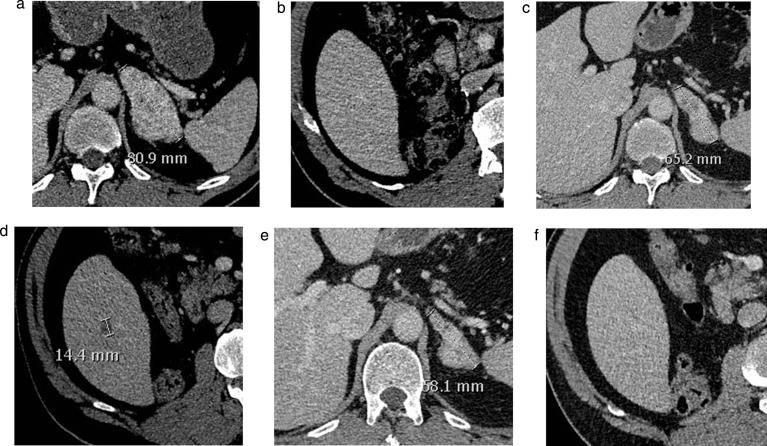

This report aims to review criteria which have been proposed for treatment evaluation in mRCC under anti-angiogenic and immune-oncologic therapies and discuss future challenges for imagers. RECIST criteria seem to only partially reflect the clinical benefit derived from anti-angiogenic drugs in mRCC. New methods of analysis propose to better evaluate response to these drugs, including a new threshold for size criteria (-10%), attenuation (Choi and modified Choi criteria), functional imaging techniques (perfusion CT, ultrasound or MRI), and new PET radiotracers. Imaging of progression is one of the main future challenges facing imagers. It is progression and not response that will trigger changes in therapy, therefore it is tumour progression that should be identified by imaging techniques to guide the oncologist on the most appropriate time to change therapy. Yet little is known on dynamics of tumour progression, and much data still needs to be accrued to understand it. Finally, as immunotherapies develop, flare or pseudo-progression phenomena are observed. Studies need to be performed to determine whether imaging can distinguish between patients undergoing pseudo-progression for which therapy should be continued, or true progression for which the treatment must be changed.

本报告旨在回顾已提出的用于评估转移性肾细胞癌(mRCC)在抗血管生成和免疫肿瘤治疗下疗效的标准,并讨论影像科医生未来面临的挑战。实体瘤疗效评价标准(RECIST)似乎仅部分反映了抗血管生成药物在mRCC中带来的临床获益。新的分析方法旨在更好地评估对这些药物的反应,包括大小标准的新阈值(-10%)、衰减(Choi标准和改良Choi标准)、功能成像技术(灌注CT、超声或MRI)以及新的正电子发射断层显像(PET)放射性示踪剂。疾病进展的影像学评估是影像科医生未来面临的主要挑战之一。是疾病进展而非反应会引发治疗的改变,因此应由成像技术识别肿瘤进展,以指导肿瘤学家在最合适的时间改变治疗方案。然而,目前对肿瘤进展的动态变化知之甚少,仍需积累大量数据来了解这一情况。最后,随着免疫疗法的发展,出现了炎症或假性进展现象。需要开展研究以确定影像检查能否区分应继续治疗的假性进展患者和必须改变治疗方案的真性进展患者。